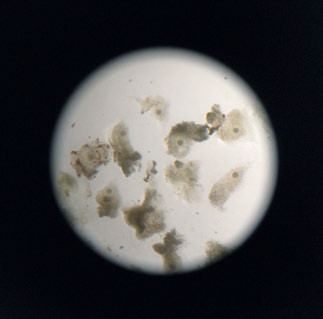

Скорее всего, потребуется ИКСИ, ICSI (Intracytoplasmic sperm injection) — инъекция сперматозоида в цитоплазму яйцеклетки. Эта технология чаще всего применяется при мужском бесплодии. Эмбриолог с помощью электронного микроскопа отбирает лучшие сперматозоиды, а затем супертонкой иглой вводит их в ооциты (в одну яйцеклетку — один сперматозоид).